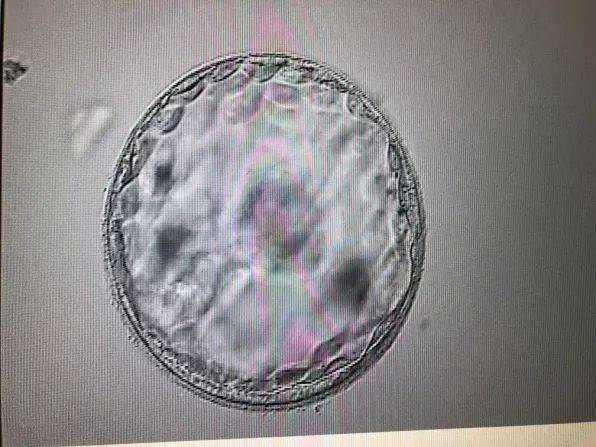

大卫验孕试纸怎么看结果图解

在解读大卫验孕试纸的结果时,我们需要关注以下两点:

1. 控制线(C线):无论是否怀孕,控制线都会出现。如果控制线清晰可见,说明试纸检测正常。

2. 检测线(T线):如果检测线与控制线一样清晰可见,说明尿液中含有hCG,即怀孕;如果检测线颜色较淡或没有出现,说明没有怀孕。

以下是一个具体的图解示例:

```

控制线(C线):清晰可见

检测线(T线):清晰可见

结果:怀孕

检测线(T线):较淡或没有出现

结果:未怀孕